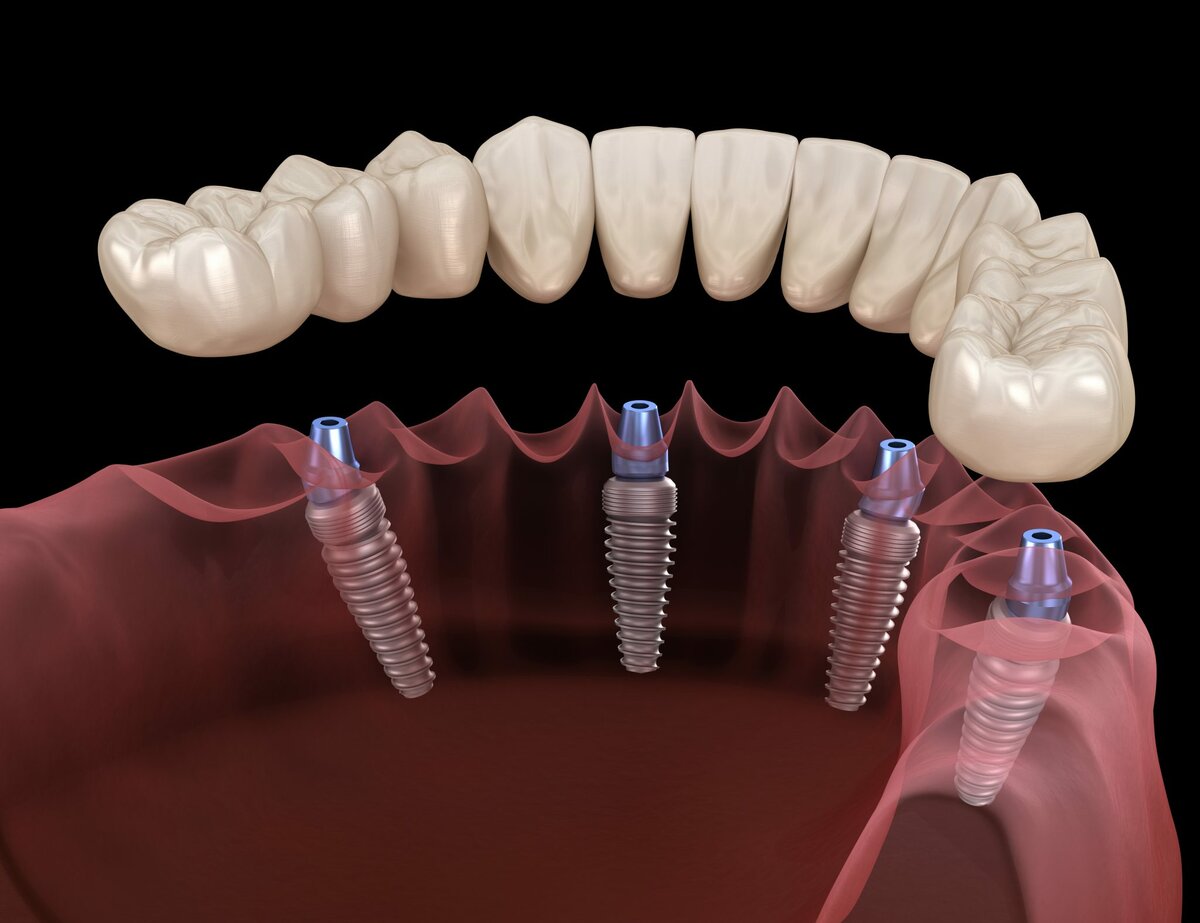

۳. کاشت پایه ایمپلنت – همان لحظه (۳۰ تا ۴۵ دقیقه)

بعد از اینکه دندان کشیده شد و استخوان آماده شد، پایه تیتانیومی در همان جلسه کاشته میشود.

نکات مهم:

- پایه باید بسیار محکم در استخوان فیکس شود

- زاویه کاشت باید دقیق باشد

- اندازه ایمپلنت باید مناسب باشد

- هیچگونه التهاب شدید نباید وجود داشته باشد

اگر تثبیت اولیه به اندازه کافی قوی نباشد، ایمپلنت فوری انجام نمیشود.

۴. نصب دندان موقت — همان روز!

در این مرحله یک تاج موقت (معمولاً از جنس آکریل) روی پایه نصب میشود.